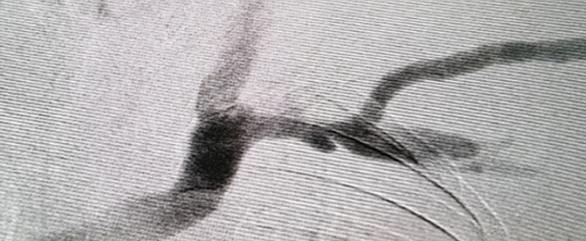

투석혈관 관리와 치료하기 투석혈관

풍선시술 시술 전

풍선시술 시술 후